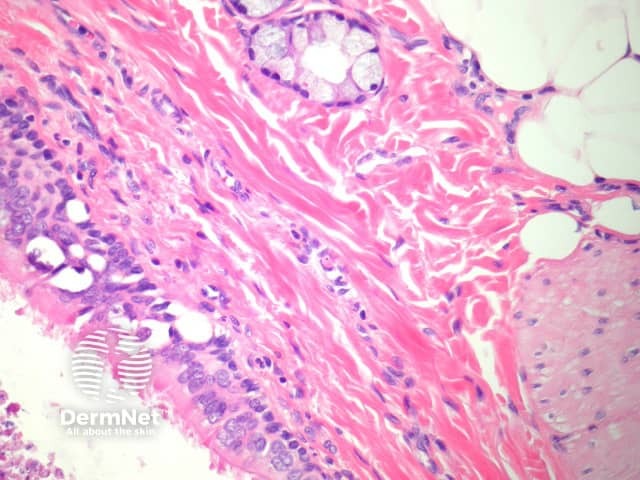

The lining of the cyst is typically ciliated (figure 3, arrows) and may be columnar or cuboidal. Squamous metaplasia is common. In the wall, it is very common to find smooth muscle and respiratory-type mucous glands (figure 4). Cartilage is another common finding in the wall.

Figure 3

Figure 4